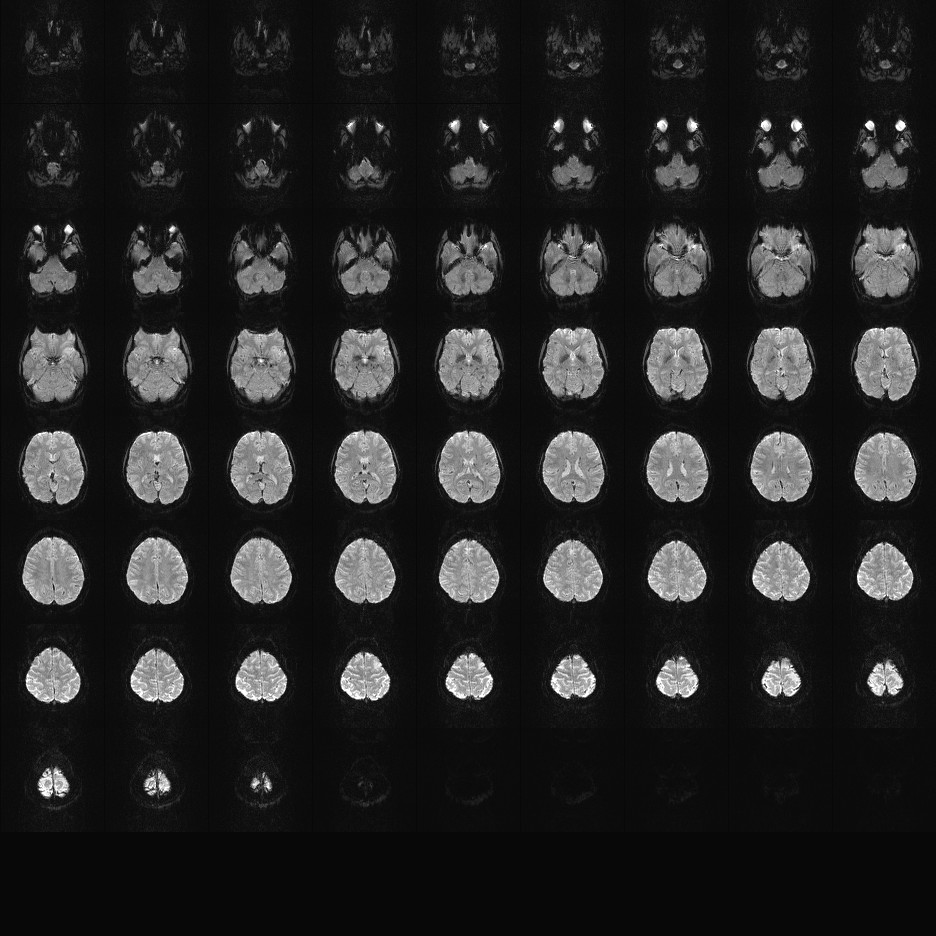

Multi-banded RF pulses can be used to accelerate volume coverage along the slice direction by simultaneously exciting and acquiring multiple slices and subsequently unaliasing them using parallel imaging principles and the spatial information available in multi-channel RF array coils.

This allows for a direct reduction in the volume TR by the number of simultaneously excited slices (i.e., the multiband (MB) factor or the slice acceleration factor).